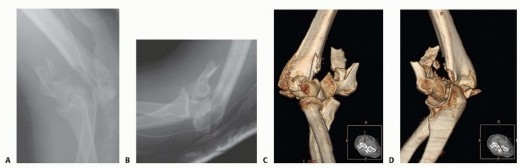

DEFINITION This injury was initially reported by Giovanni Monteggia in 1814 as a fracture of the ulna associa…

PATIENT HISTORY AND PHYSICAL FINDINGS Distal humerus fractures occur in two age groups: Younger patients who …